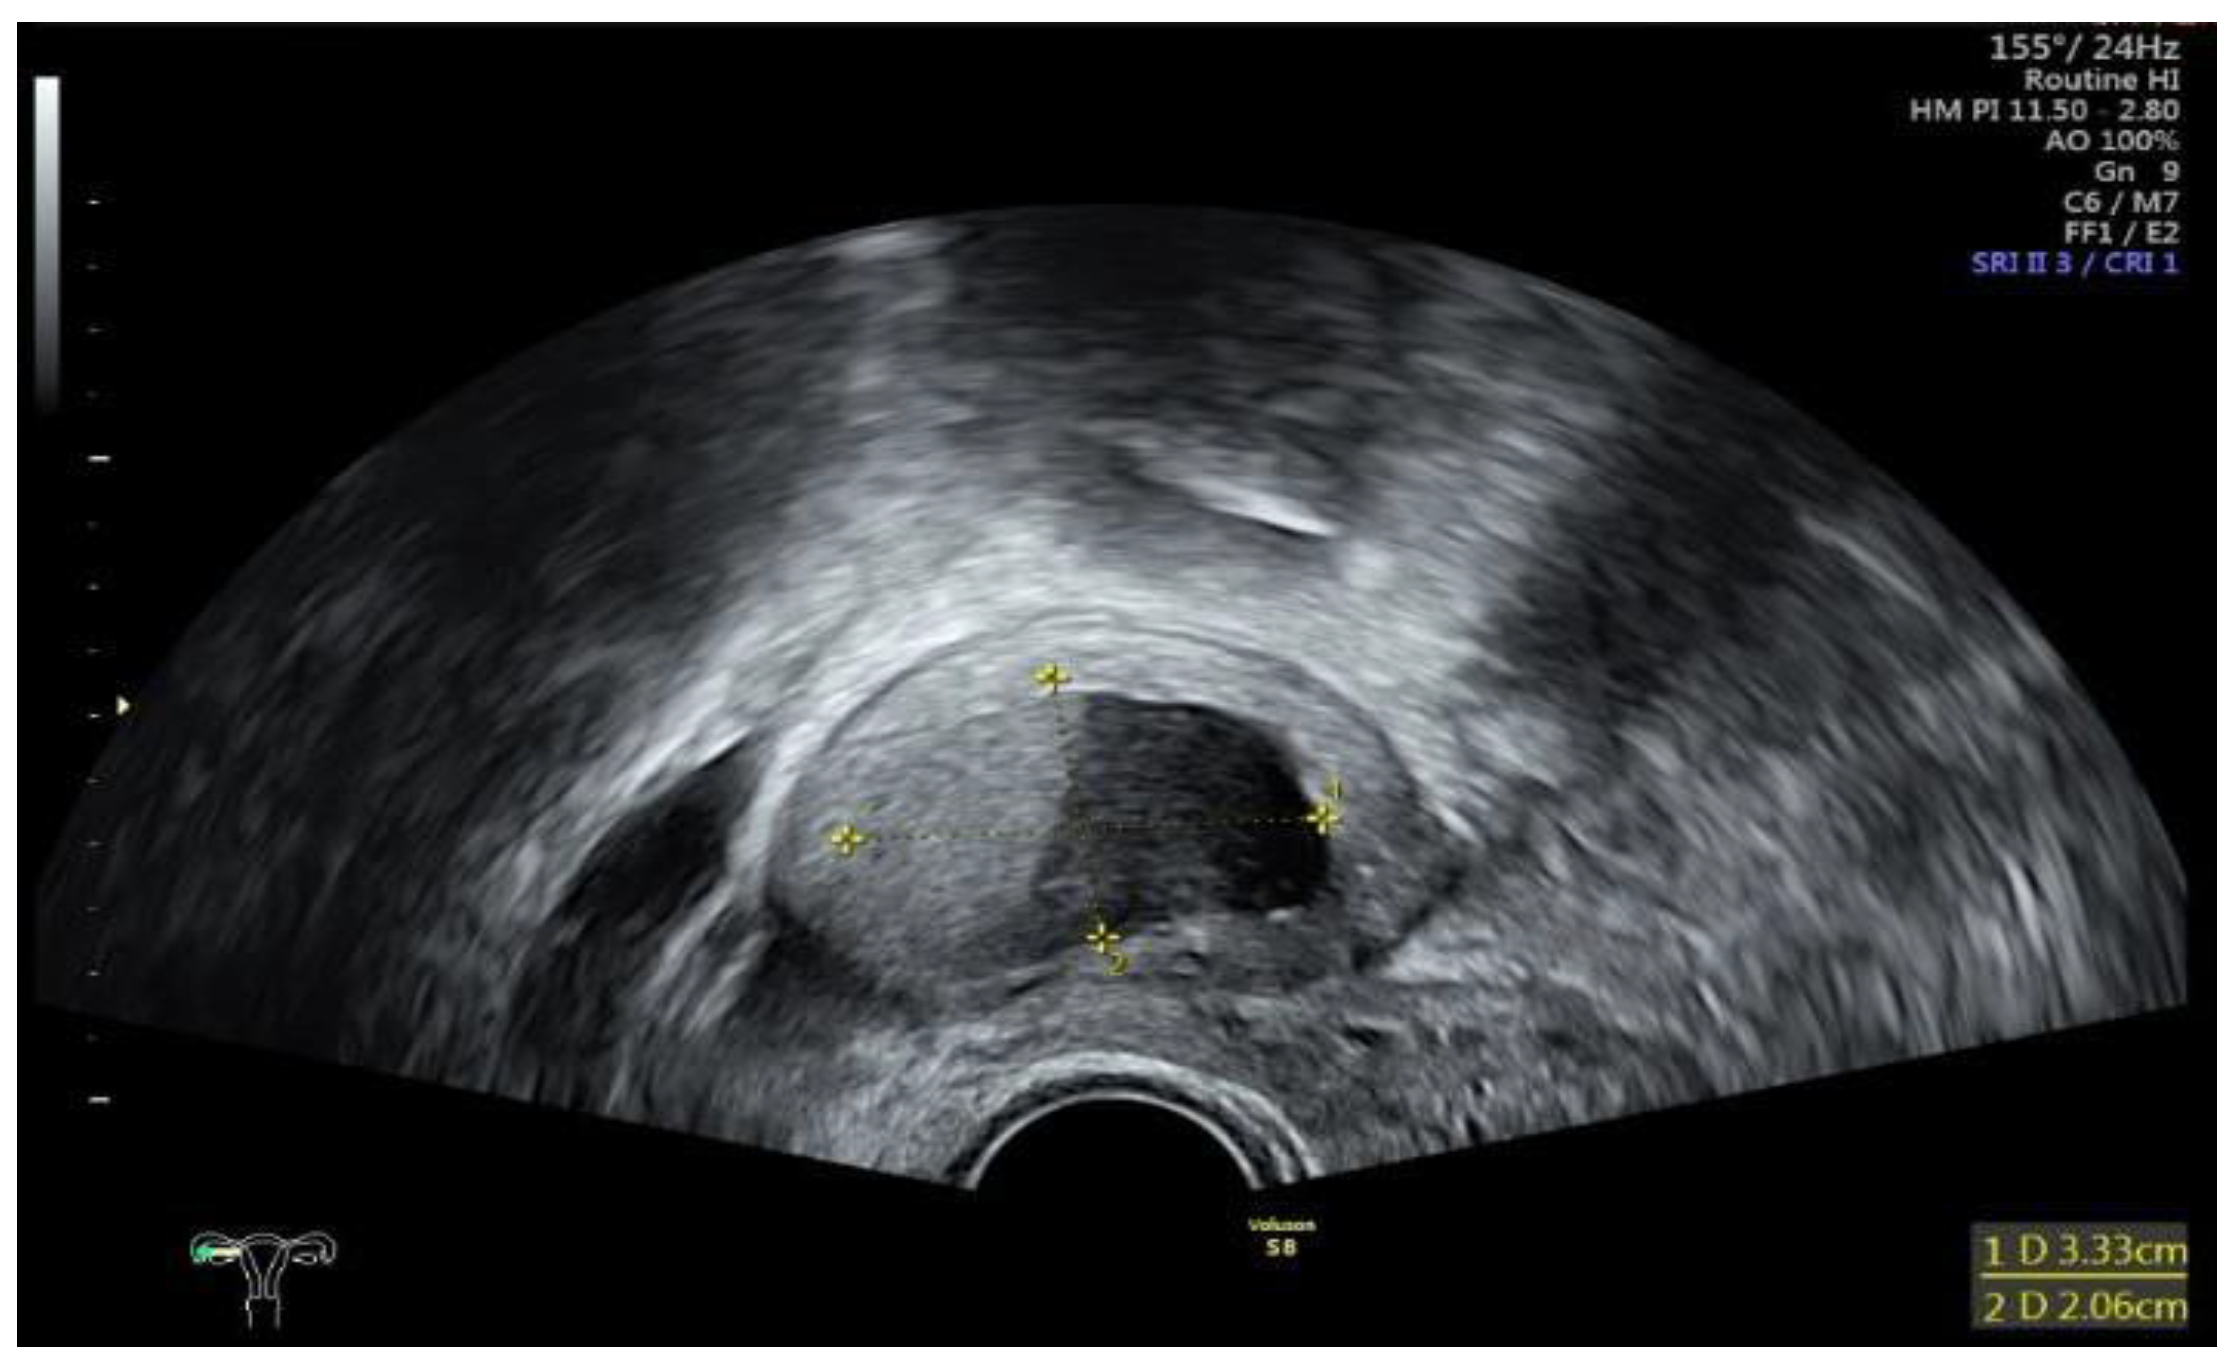

Data collection: The patients’ backgrounds, clinical symptoms at admission, sonographic and laboratory assessment, as well as intraoperative findings were recorded. Patient demographic data included age, menopausal status, presence of dysmenorrhea, history of endometriosis surgery, and use or non-use of hormonal downregulation therapy for endometriosis. Pre-operative laboratory tests included white blood cell (WBC) count, serum C-reactive protein (CRP) level, and serum CA125 level, and all patients underwent transvaginal sonography (Figure 1) on admission as part of the emergency diagnostic assessment. The maximal diameter and the location of the endometriomas were noted. The intraoperative findings included the location of the ruptured endometriomas (Figure 2 and Figure 3), the presence and classification of endometriosis according to the rASRM [16] and #ENZIAN [17] systems, and, lastly, total blood loss.

Figure 1. Sonographic display of a ruptured endometrioma of the right ovary in a 28-year-old woman with sudden onset of abdominal pain.